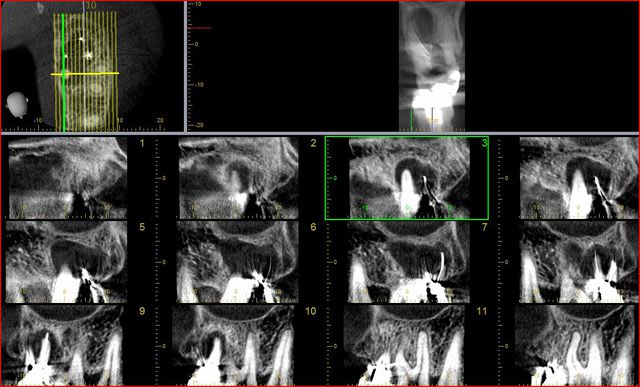

comme j'ai une comparaison de ma propre tronche avec une morita r100 et un conne beam de 120 kv (position assise) j'en profite pour vous montrer la différence entre les deux au même endroit.

à vous de juger...

Capture cone beam 120kv ffse9u - Eugenol

Capture morita ja7x4o - Eugenol